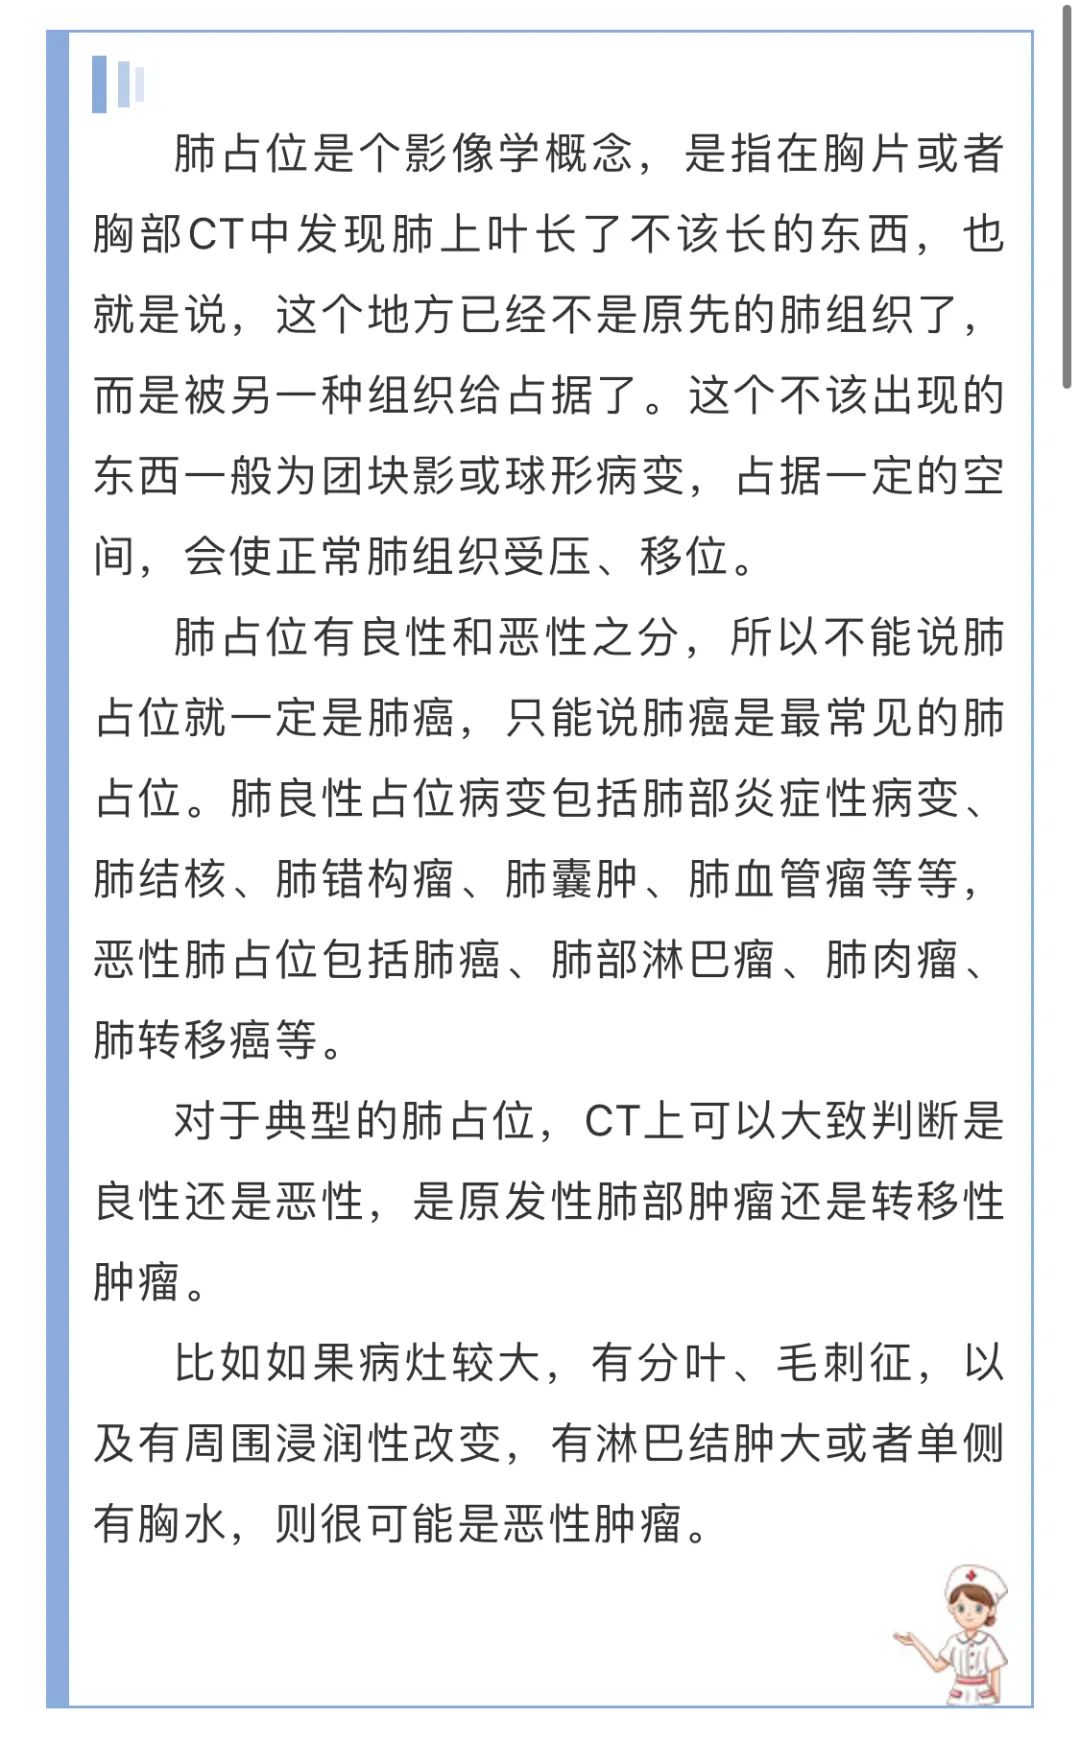

▲左肺上叶磨玻璃密度影